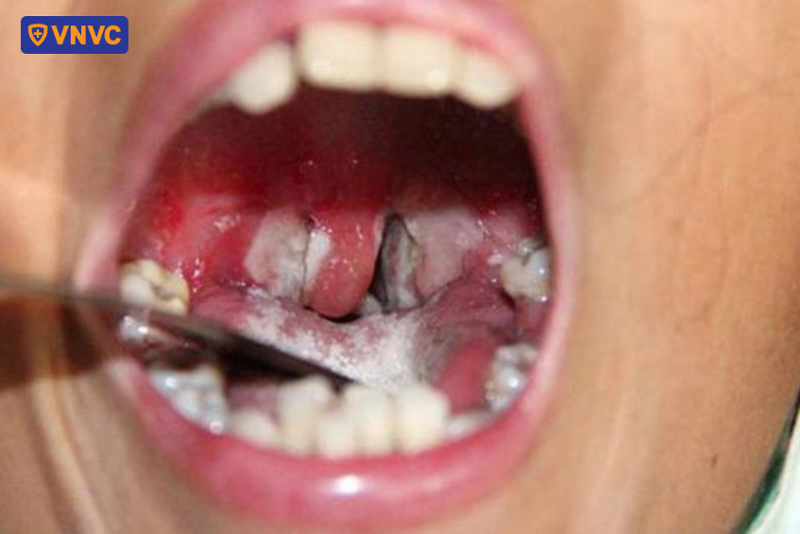

Hình ảnh đặc trưng của bạch hầu giúp phân biệt với cảm cúm

Bệnh bạch hầu có những hình ảnh đặc trưng giúp phân biệt với cúm, đặc biệt là các dấu hiệu liên quan đến đường hô hấp và hệ thống bạch huyết. Dưới đây là những hình ảnh trực quan giúp phân biệt bạch hầu và cảm cúm:

Các dấu hiệu ban đầu thường xuất hiện từ 2 – 5 ngày sau khi tiếp xúc với vi khuẩn, bao gồm đau họng, sốt, sưng hạch cổ và cảm giác mệt mỏi. Sau 2 – 3 ngày, mô chết trong đường hô hấp tạo thành lớp màng màu xám dày, có thể bao phủ các mô ở mũi, amidan và cổ họng, gây khó khăn trong việc thở và nuốt. (1)